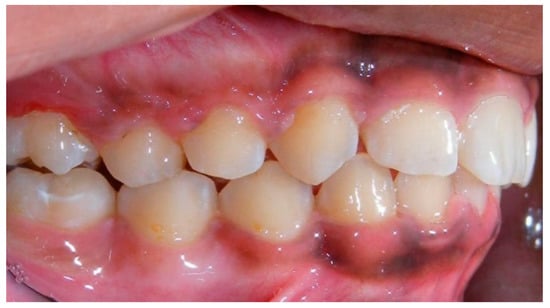

- Assessment of proposed sites of temporary anchorage device (TAD). Figure 11, Figure 12, Figure 13 and Figure 14 show correction of the Class II molar relationship using a temporary anchorage device. Figure 11 shows a pre-treatment intraoral photograph of the right side. The Class II molar relationship can be observed. Figure 12 shows coronal, sagittal and axial views, as well as a volume rendering of CBCT that was acquired in order to assess the site of the temporary anchorage device. Figure 13 shows an intraoral photograph of the right side, in which the TAD was placed mesial to the maxillary first molar, and a power chain was attached from this TAD to a hook placed distal to the lateral incisor. Figure 14 shows a post-treatment intraoral photograph showing improvement of the Class II molar relationship after removal of all orthodontic appliances.